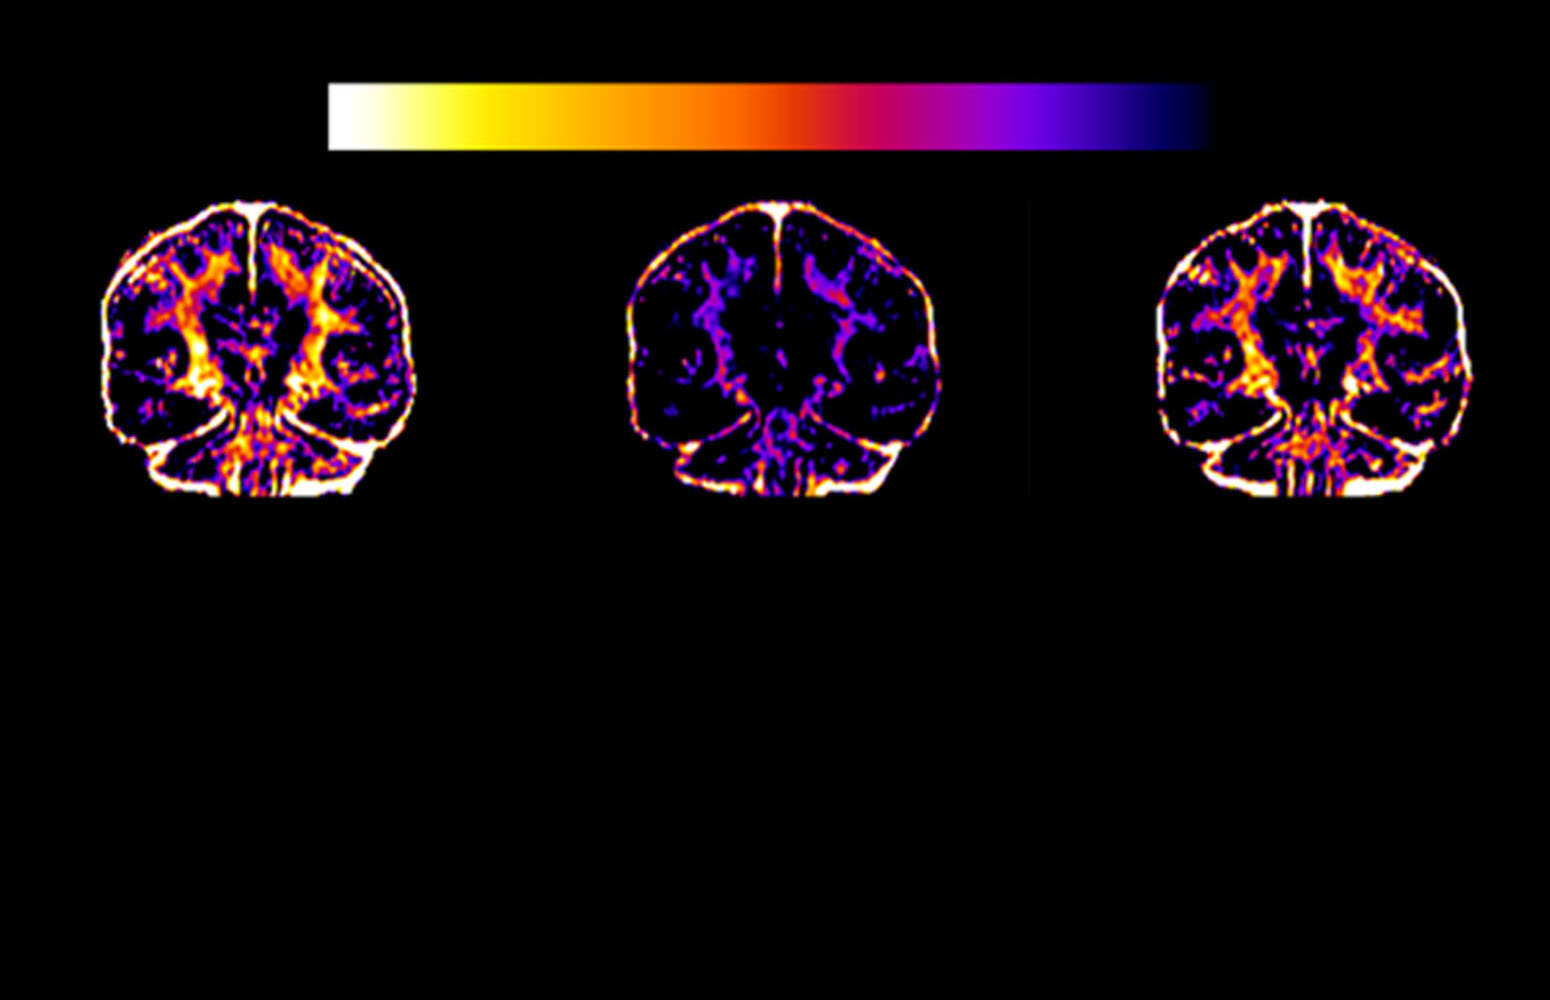

El trabajo, publicado en Nature Metabolism, una de las revistas especializadas del grupo Nature, analiza qué ocurre en el cerebro durante el esfuerzo extremo de una maratón. A partir de imágenes de resonancia magnética realizadas a corredores antes y después de la prueba, los investigadores descubrieron que, ante la escasez de glucosa, el cerebro utiliza temporalmente la mielina —la sustancia que recubre las neuronas— como fuente de energía. La buena noticia es que esta reducción es reversible y se recupera por completo en un plazo de dos meses con descanso y una dieta adecuada.

“Los resultados indican que correr una maratón no daña el cerebro. Los cambios observados en la mielina son sutiles y transitorios, y se revierten de forma natural en pocas semanas. Lejos de evidenciar una lesión, nuestros datos ponen de manifiesto la extraordinaria resiliencia del cerebro humano y su capacidad para adaptarse y recuperarse incluso ante situaciones de estrés físico extremo”, puntualiza Carlos Matute